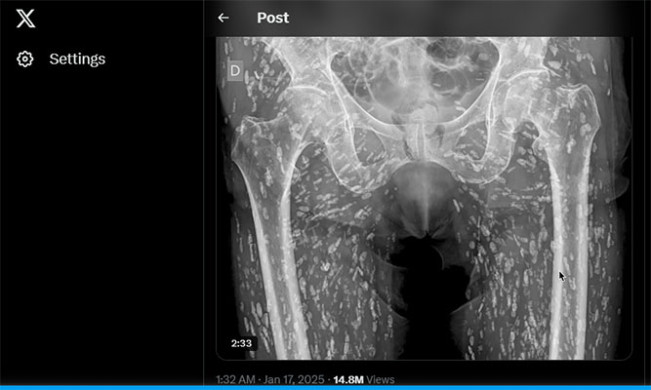

Hasil rontgen yang dibagikan dokter Sam Ghali di akun X (twitter)-nya menunjukkan ratusan telur cacing pita bersarang di tubuh bagian bawah pasien/Foto: akun X Sam Ghali

Seorang dokter UGD baru-baru ini membagikan "salah satu hasil rontgen paling gila yang pernah dilihatnya," yang memperlihatkan tubuh bagian bawah seseorang dipenuhi ratusan telur cacing pita yang mengapur. Hasil rongen itu dibagikannya di X (twitter).

Sam Ghali, seorang dokter UGD yang mengkhususkan diri dalam keadaan darurat kardiovaskular dan radiologi darurat, baru-baru ini membagikan hasil rontgen yang tidak biasa dari area panggul seorang pasien yang memperlihatkan tubuhnya dipenuhi ratusan bintik putih.

Semua itu adalah telur cacing pita yang telah mengeras dan tersangkut di jaringan lunak tubuh bagian bawahnya. Menariknya, pasien tersebut tidak pernah tahu tentang sistiserkosis yang dideritanya dan ia baru mengetahuinya saat ia datang untuk melakukan rontgen setelah terjatuh dan mengalami nyeri pinggul.

“Ini adalah kondisi yang dikenal sebagai sistiserkosis, pada dasarnya ini adalah kista larva taenia solium, yang juga dikenal sebagai cacing pita babi,” kata Ghali di X (Twitter). “Kista ini dapat menyebar ke seluruh tubuh, terutama ke jaringan otot dan jaringan lunak di pinggul dan kaki.” Kecuali jika mencapai otak, telur-telur yang mengalami pengapuran ini pada dasarnya tidak berbahaya, mereka tidak lagi dapat bertahan hidup, tetapi jika sekadar memikirkan akan dihinggapi ratusan kista seperti butiran beras ini saja sudah tidak masuk akal, Anda sebaiknya menjauhi daging babi dan ikan mentah atau setengah matang, demi berjaga-jaga.